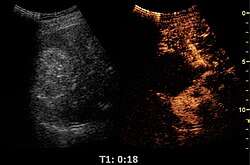

- Lesion Characterization: contrast-enhanced ultrasound plays a role in the differentiation between benign and malignant focal liver lesions. This differentiation relies on the observation[15] or processing[16][17] of the dynamic vascular pattern in a lesion with respect to its surrounding tissue parenchyma.